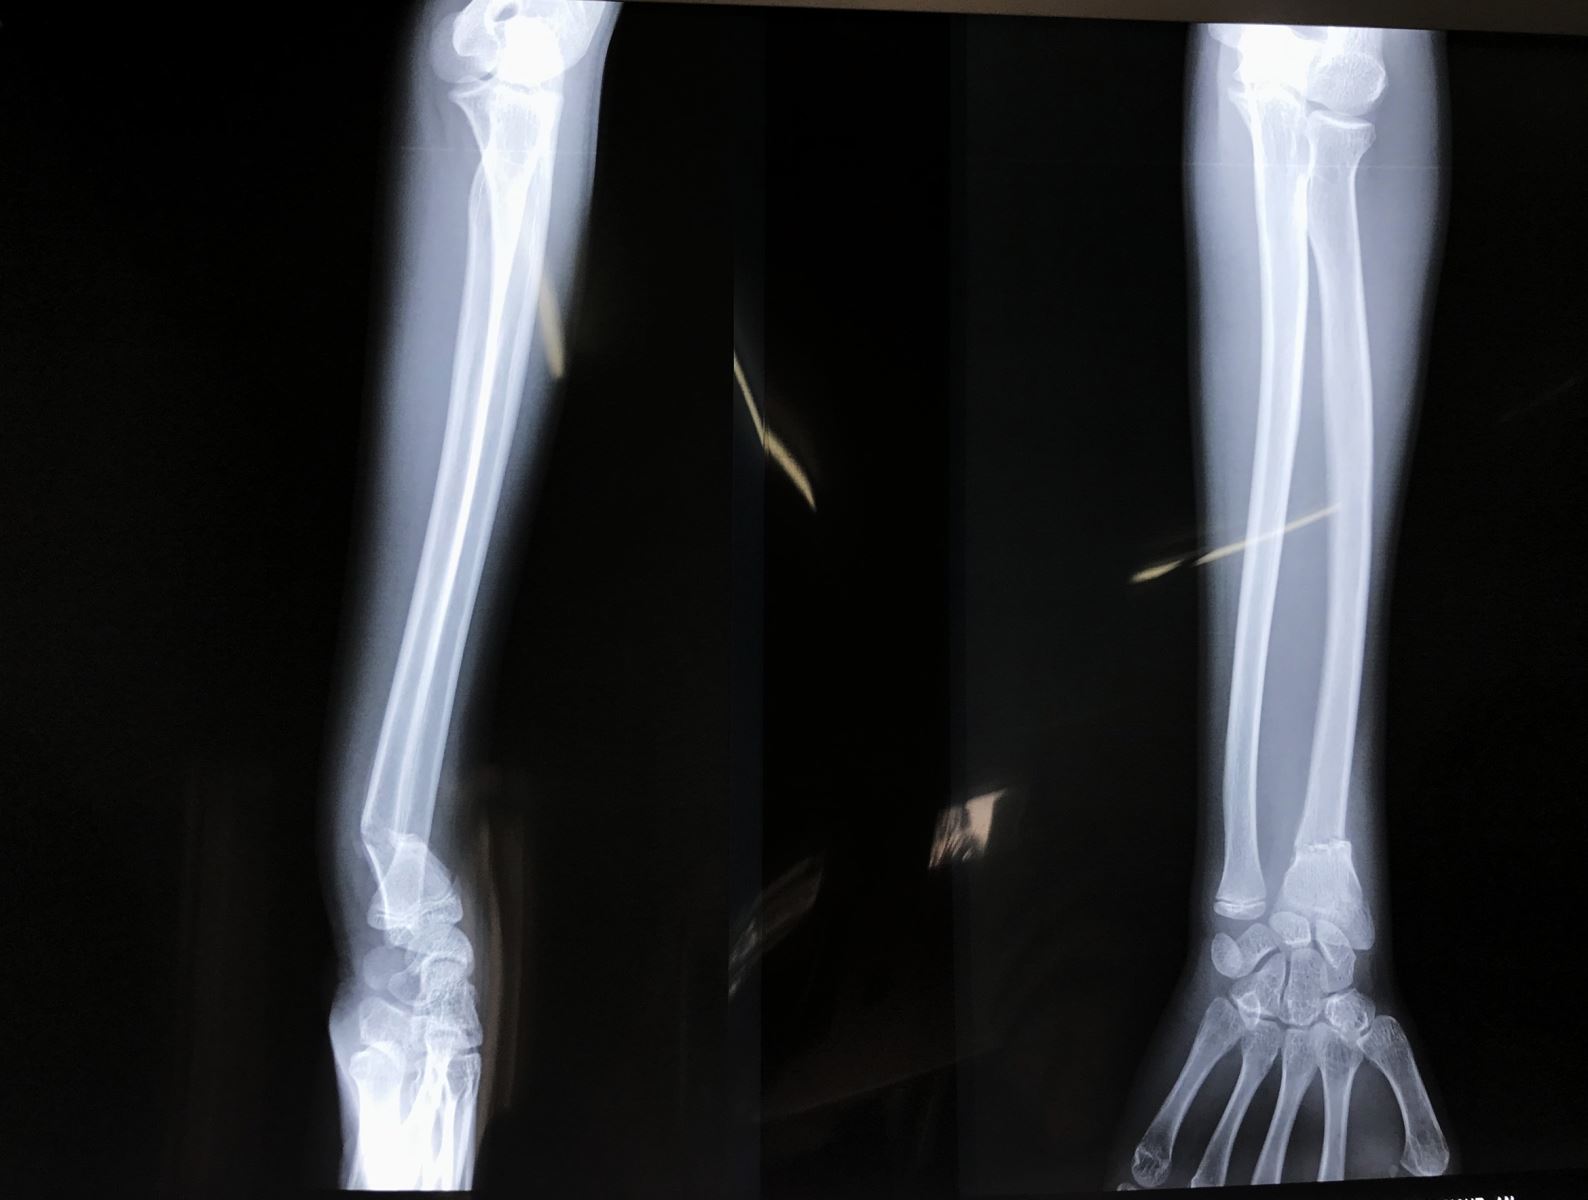

- X Quang cổ tay, cẳng tay thẳng nghiêng

X Quang khuỷu tay thẳng nghiêng nếu có đau về phía khuỷu hoặc có gãy thân xương